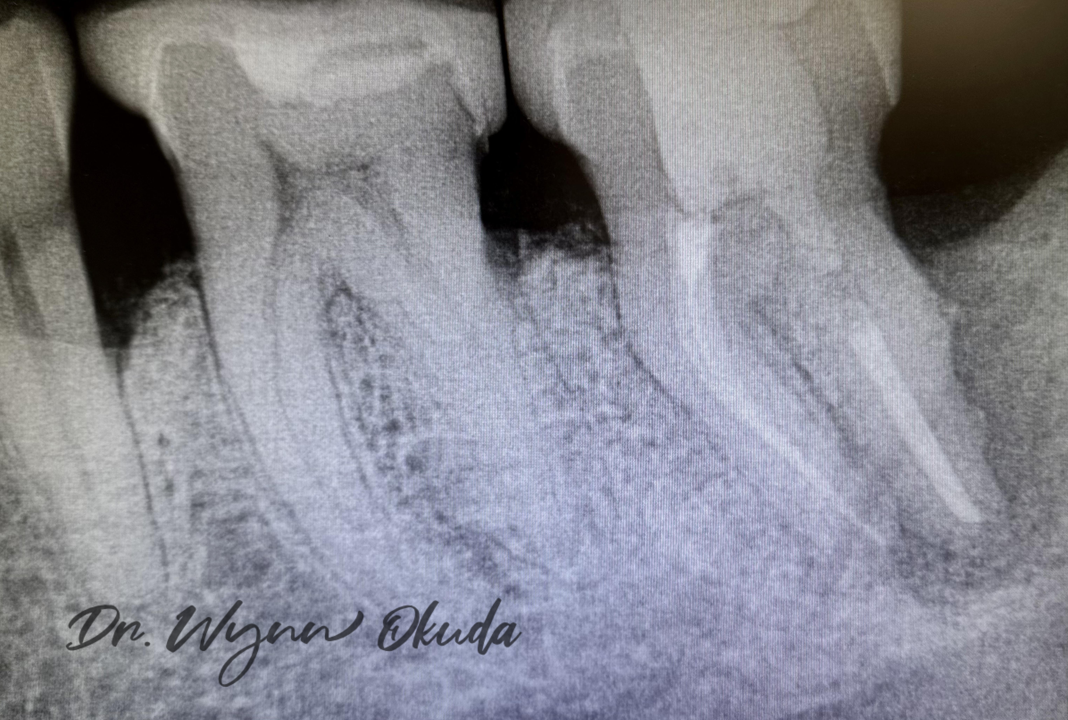

One of the most remarkable cases in my practice involved a 65-year-old patient with a severely compromised lower molar. Due to extensive distal root bone loss, the tooth was deemed unsalvageable by endodontic evaluation. (Figure 3)

The patient, however, wanted to save the tooth.

Following root canal therapy, I performed scaling and root planing using a mini-flap approach to meticulously remove granulation tissue. I then utilized the BIOLASE Waterlase iPlus with radial and side-firing tips to thoroughly sterilize the root surface and surrounding bony defect.

After de-epithelialization and decortication, a bone graft was placed to encourage regeneration.